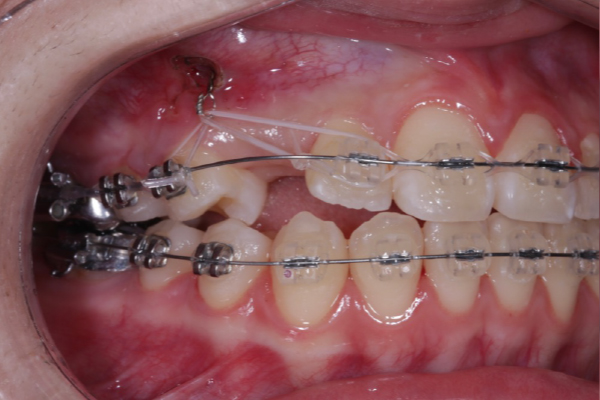

埋まっている犬歯の牽引

残存していた乳犬歯を抜歯後、埋伏している上顎犬歯に対して外科的開窓を行い、矯正装置を用いた牽引を開始しました。

歯列に大きな叢生が認められなかったため、全体的な歯列バランスを維持しながら、スペース管理を行い慎重に犬歯の誘導を進めました。

定期的に歯の移動方向や歯周組織の状態を確認しながら治療を行いました。